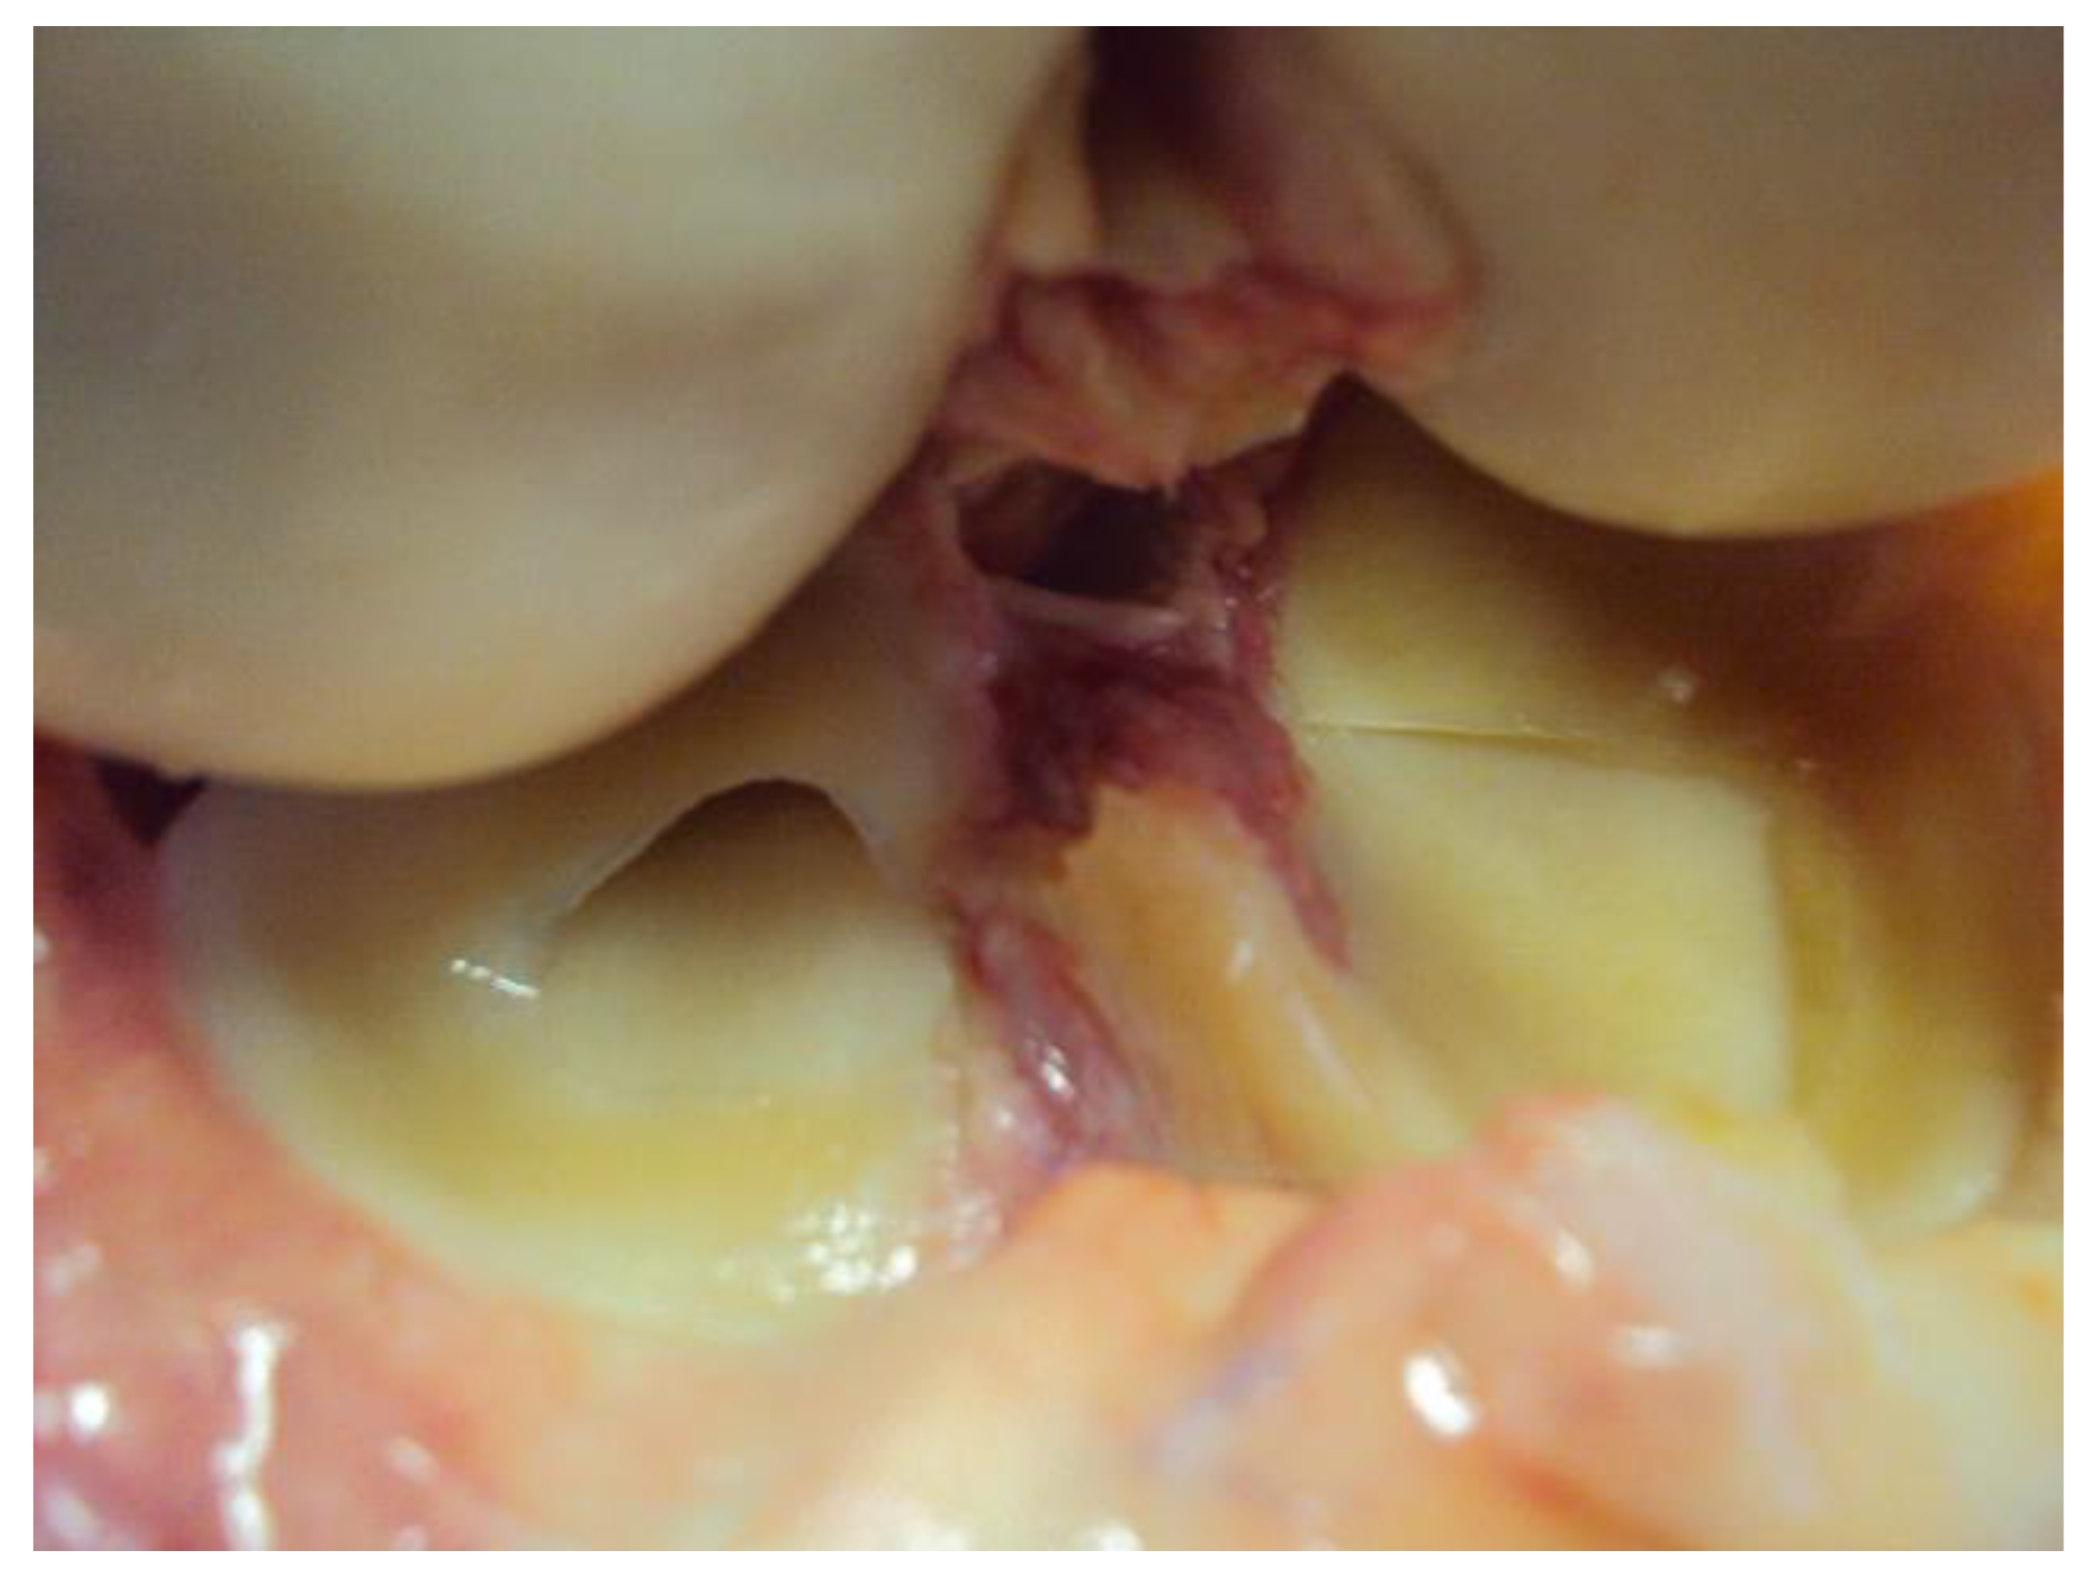

Figure 2.

A preview image of intersection of the ACL in an anatomical specimen—arthrotomy.